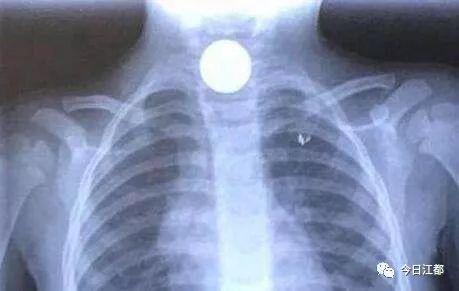

张月玲了解情况后,立即为孩子安排了胸部拍片检查,结果正如她所料,影片显示有金属物卡在幼儿食管上段的狭窄处。后经耳鼻喉科会诊,孩子被迅速转入耳鼻喉科病房,科主任肖旭东拿着片子认真看了起来,此时他心中不禁产生了一个疑惑,一般而言硬币都是圆形的,但在影片中呈现的却是椭圆状,他大胆推测孩子可能误吞了不止一枚硬币。本来孩子的食管就细,这还卡住了多枚硬币,手术难度瞬间大增。